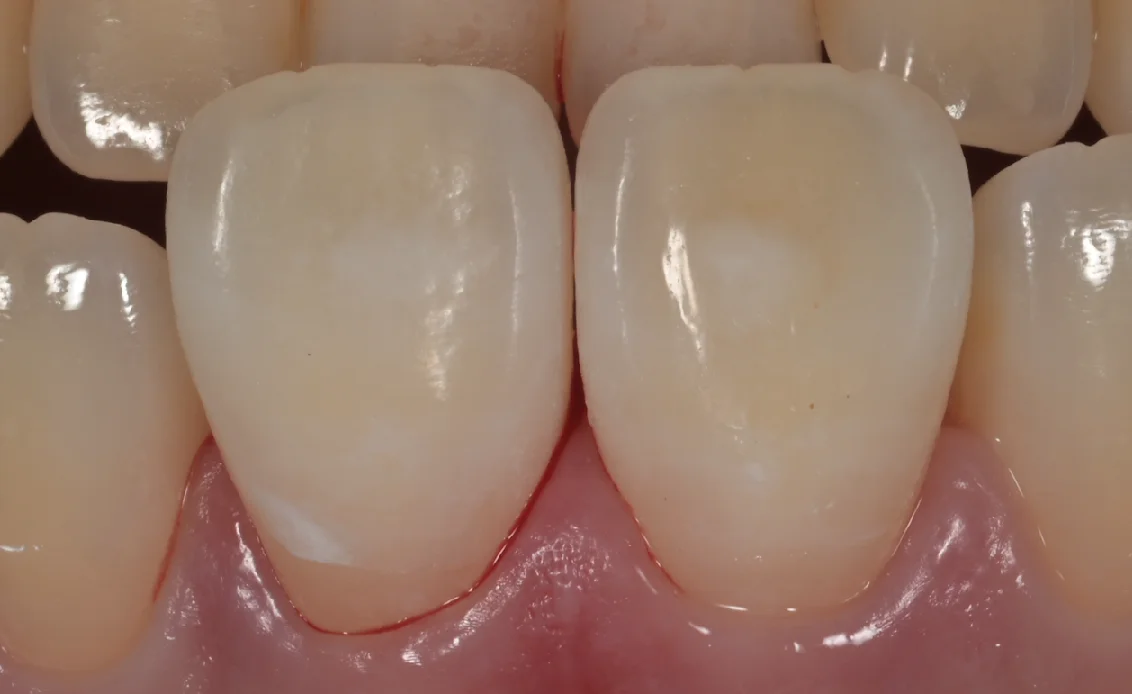

さて、ラバーダムを外したのがこちらになります。

随分と目立たなく、違和感が少なくなったのが分かるかと思います。

ゴムのマスクを強く歯茎に押し込むので一部出血していますが、出血自体は5分くらいで治って違和感も1〜2日で消えますので、そこはご安心ください。

色は若干残ってしまいましたが、患者さん本人はホワイトスポットが気にならないレベルに薄くなって非常に喜んでいただけました。